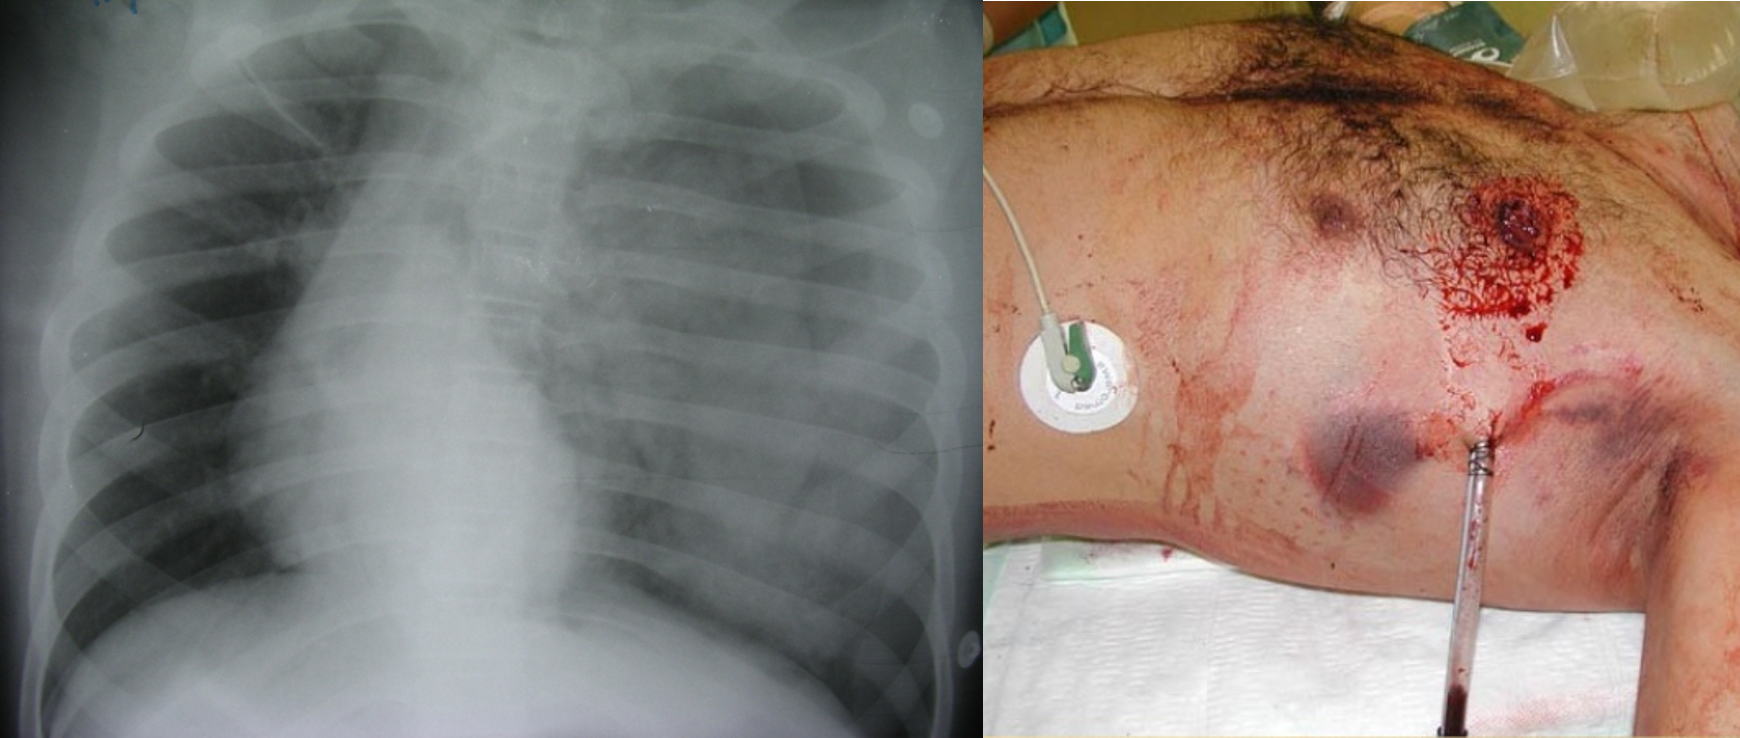

Massive hemothorax

- Accumulation of >1.5L of blood

- Cause: Disruption of large vessel

- Flat neck vein

- Dullness on percussion

- No breath sound on auscultation

- Shock

- Management:

- Chest tube in 5th space.

- Fluid resuscitation.

- Thoracotomy if significant bleeding continues.